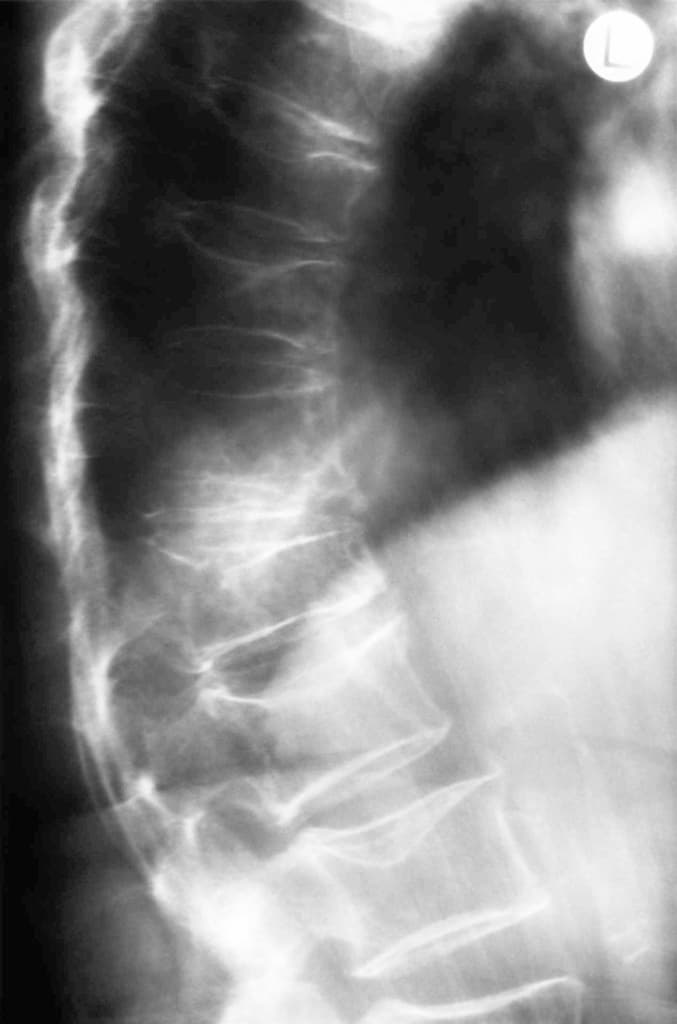

Des dorso-lombalgies d’intensité croissante ont empêché une jeune mère de s’occuper de son nourrisson de douze semaines. Son gynécologue a conclu à des tensions musculaires, mais l’IRM a révélé une cause bien plus sévère.

De telles atteintes des corps vertébraux ne s’observent en général que chez les séniors. Mais elle peut également toucher la femme jeune dans le cadre d’une ostéoporose associée à la grossesse.